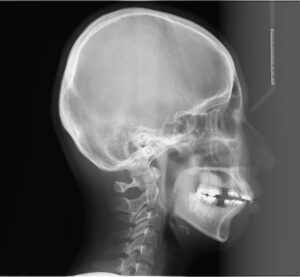

これを治療計画に盛り込むと

今回のケースは

上の歯は両側4番目の歯をスペースとしていただき

下の歯は乳歯があるのでそれをスペースとしました。

この治療計画で、歯列矯正のソフトウェアで

横顔の画像をシュミレートするとこのようになります。